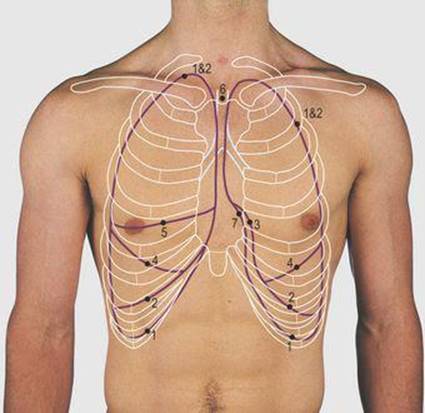

4.8 Surface markings of the lungs and pleura

1 Pleural markings

2 Lung markings

3 Cardiac notch

4 Oblique fissure

5 Horizontal fissure

6 Trachea

7 Mediastinal pleural recess

Pleura and lungs (Figs 4.8, 4.9)

Each pleural cavity extends superiorly 3 cm above the middle of the medial third of the clavicle and the possibility of damage in surgical procedures in the neck is considered in Figure 3.17 (p. 28). The anterior border of the pleural cavity reaches the midline at the sternal angle. The left moves away from the midline at the fourth costal cartilage, the right at the sixth costal cartilage and both cross the midclavicular line at the eighth costal cartilage, the midaxillary line at the 10th cartilage and pass along the line of the 12th rib posteriorly (to be remembered by the even numbers). These markings indicate the extent of the pleura around the outer chest wall. The diaphragm bulges up into each pleural cavity from below, reaching as high as the fourth intercostal space on the right side and the fifth on the left. The cardiac notch on the left side, at the fourth costal cartilage, is produced by the heart which bulges into the medial surface of both cavities but more markedly on the left.

The lung markings coincide with those of the pleura, except inferiorly, where they do not extend down into the lateral recesses and are approximately two rib spaces higher. The oblique fissure of each lung, separating its upper and lower lobes, follows a line from the third thoracic vertebra to the sixth costochondral junction. The horizontal fissure, dividing the right upper and middle lobes, follows a horizontal line from the oblique fissure to the fourth right costal cartilage. The position of the trachea in the neck is always identified when examining the lungs and pleural cavities. It should lie in the midline deep to the sternal notch and a finger passes into the slight hollow on either side of it. The trachea divides at the level of the sternal angle.